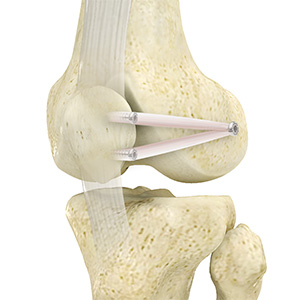

Hamstring Autograft

The anterior cruciate ligament (ACL) is one of the major stabilising ligaments in the knee. It is a strong rope-like structure located in the centre of the knee running from the femur to the tibia. When this ligament tears, it does not heal on its own and often leads to the feeling of instability in the knee.